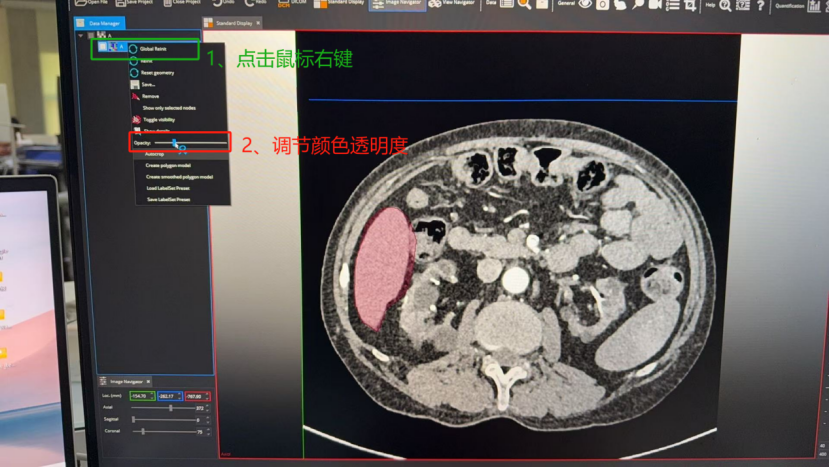

以看到我的勾勒超出肝脏区域了,此外标注的颜色太浓会影响我对标注边界的判断。所以需要对标注进行:1)淡化标注颜色;2)修改标注。

针对问题1,调节标注颜色透明度: